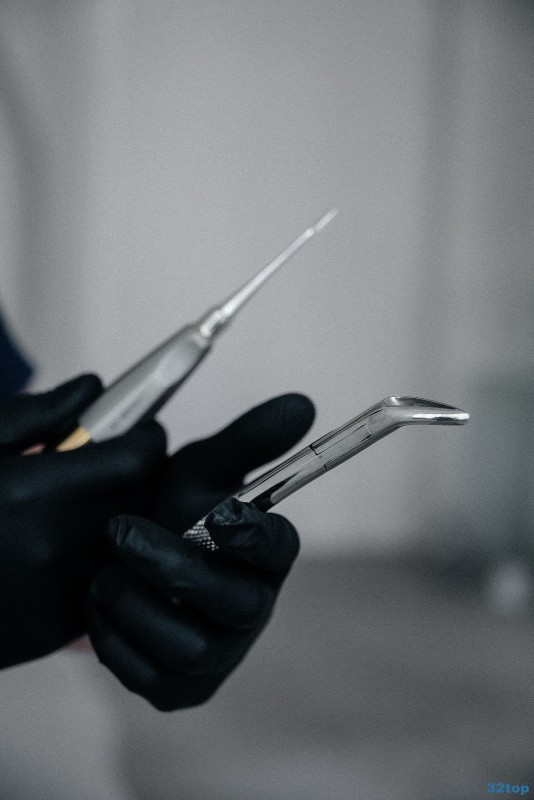

Удаление зубного камня ультразвуком в Краснодаре

Удаление зубного камня